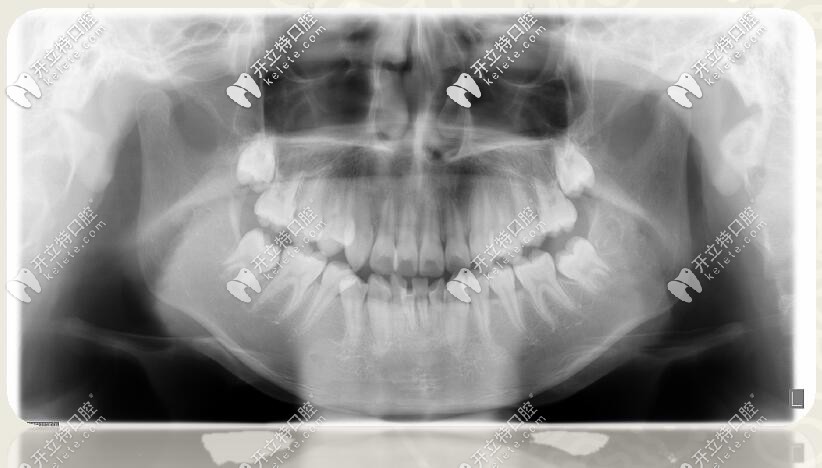

口腔全景片

口腔診斷

1、安氏Ⅱ類錯(cuò)合

2、骨性二類錯(cuò)合

3、前牙區(qū)深覆蓋、深復(fù)合

4、跨牙合

5、牙列擁擠不齊